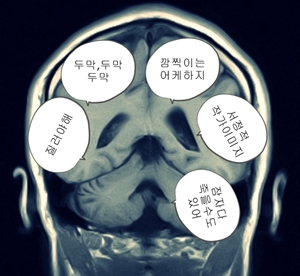

오늘 아침에 머리 MRI를 찍어 봤어요...

내 머리 속의 악마....ㅎㅎㅎㅎ;;;;;